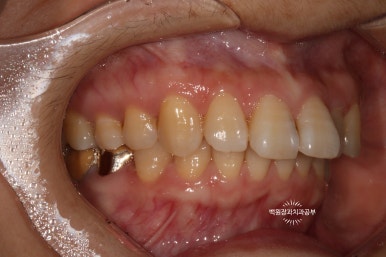

더 확실하게 보여드리기 위해 고개를 살짝 돌려서 보면..

고개를 돌려서 보면 인접면 충치를 더 잘 확인하실 수 있습니다!

집에서 확인해 보실 때도 고개를 돌려서 보셨었겠죠?